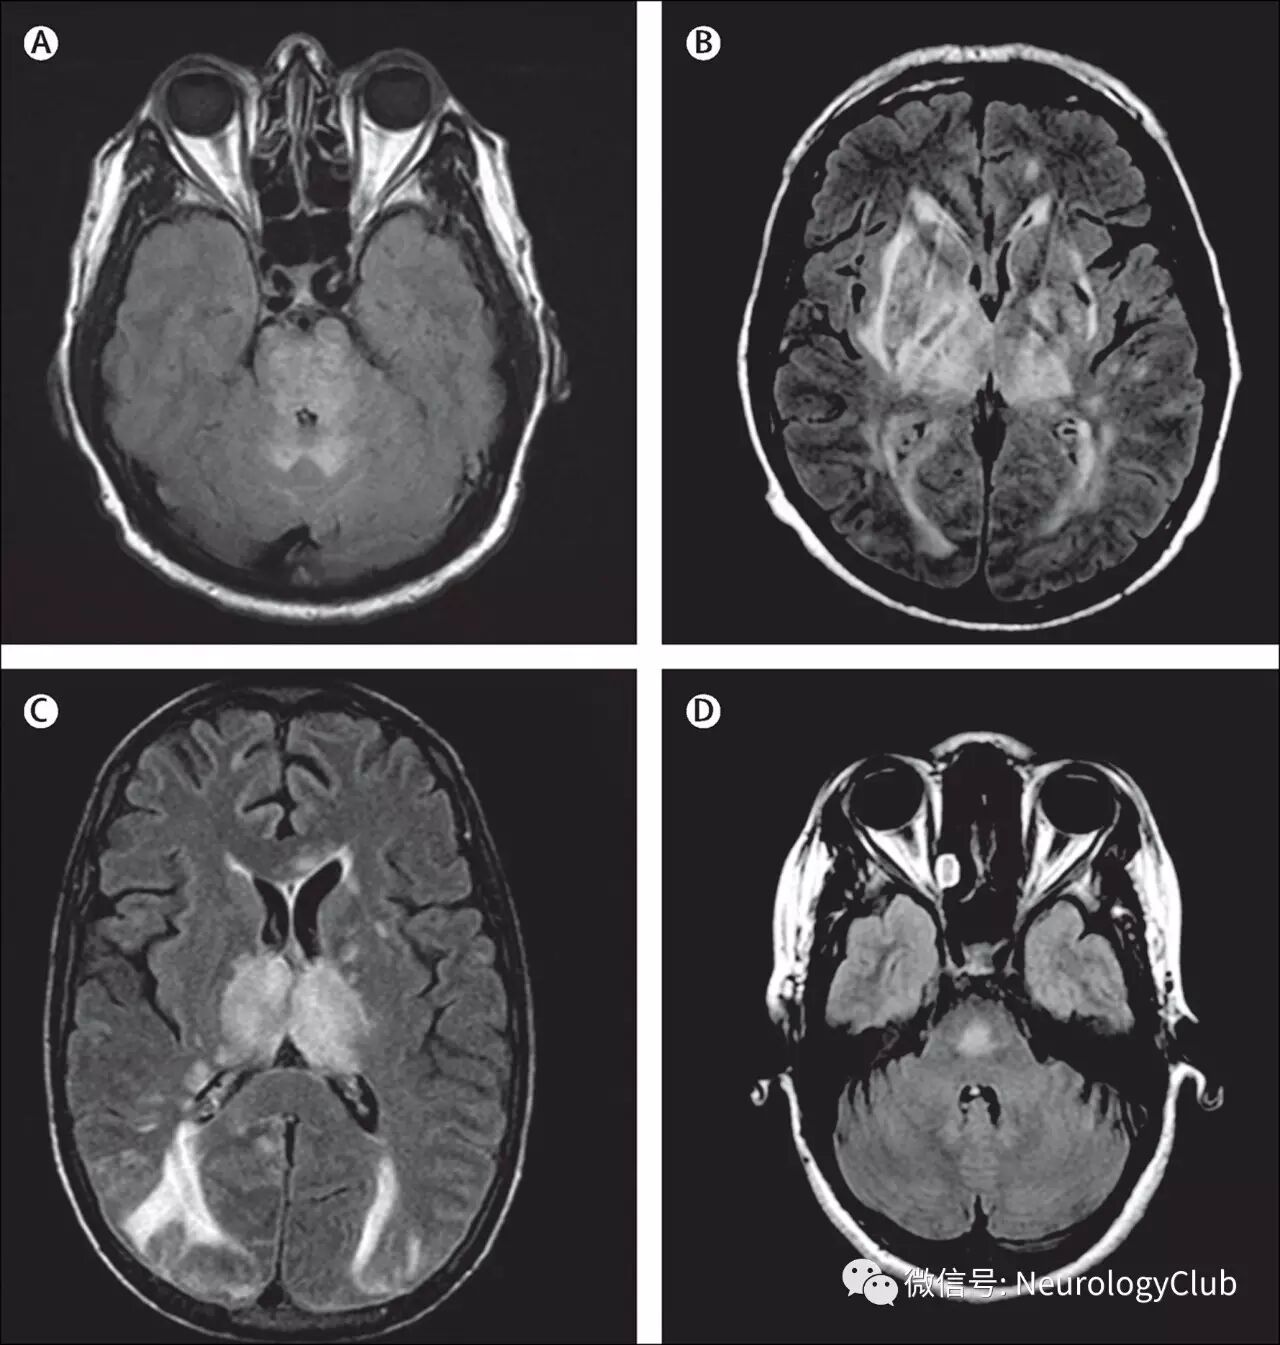

案例2:37岁男性,既往无高血压病史,因突发头痛、进展性视力下降2周入院。入院时测血压270/160mmHg。眼底镜可见出血、渗出和视乳头水肿。快速降血压治疗(ARB+利尿剂+CCB)使血压降至正常。

(图11:a-f:头颅MRI示脑干、双侧丘脑与额颞叶皮层下白质异常高信号。头痛和视觉症状2周后逐渐好转。g-l:3月后复查头颅MRI,病灶明显吸收